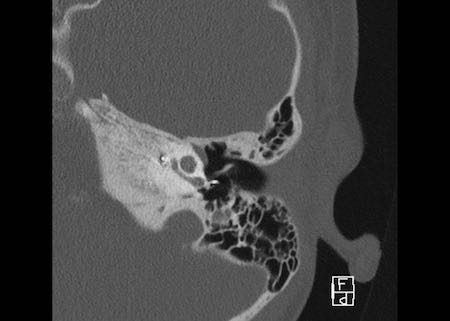

Bên trái là hình ảnh của một bé trai 16 tuổi, được khám tiền phẫu vì cholesteatoma tai phải.

Là một phát hiện tình cờ, có hình ảnh ống bán khuyên ngoài phình to (mũi tên vàng) và vắng mặt ống bán khuyên trên (mũi tên xanh dương).

Tại vị trí dự kiến của ống bán khuyên trên chỉ quan sát thấy một gờ nhỏ.

Ống bán khuyên sau bình thường.